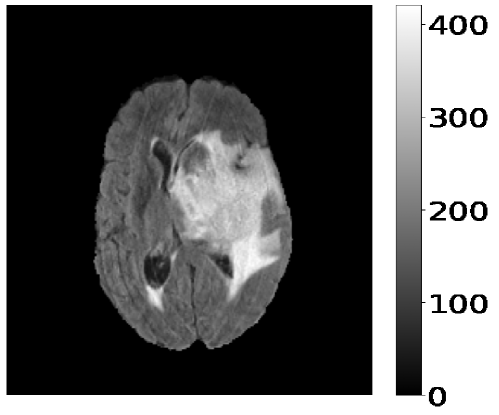

The target images have been converted into one-hot vectors. It encodes the segmentation labels as binary vectors, with each dimension corresponding to a distinct label, Edema, NET/NCR, or ET. The normalized input MR images are then stacked. The ground truth and the corresponding one-hot vectors are shown in Figure 3. These pre-processing steps ensure that the input data is in a suitable format for training the deep learning model.